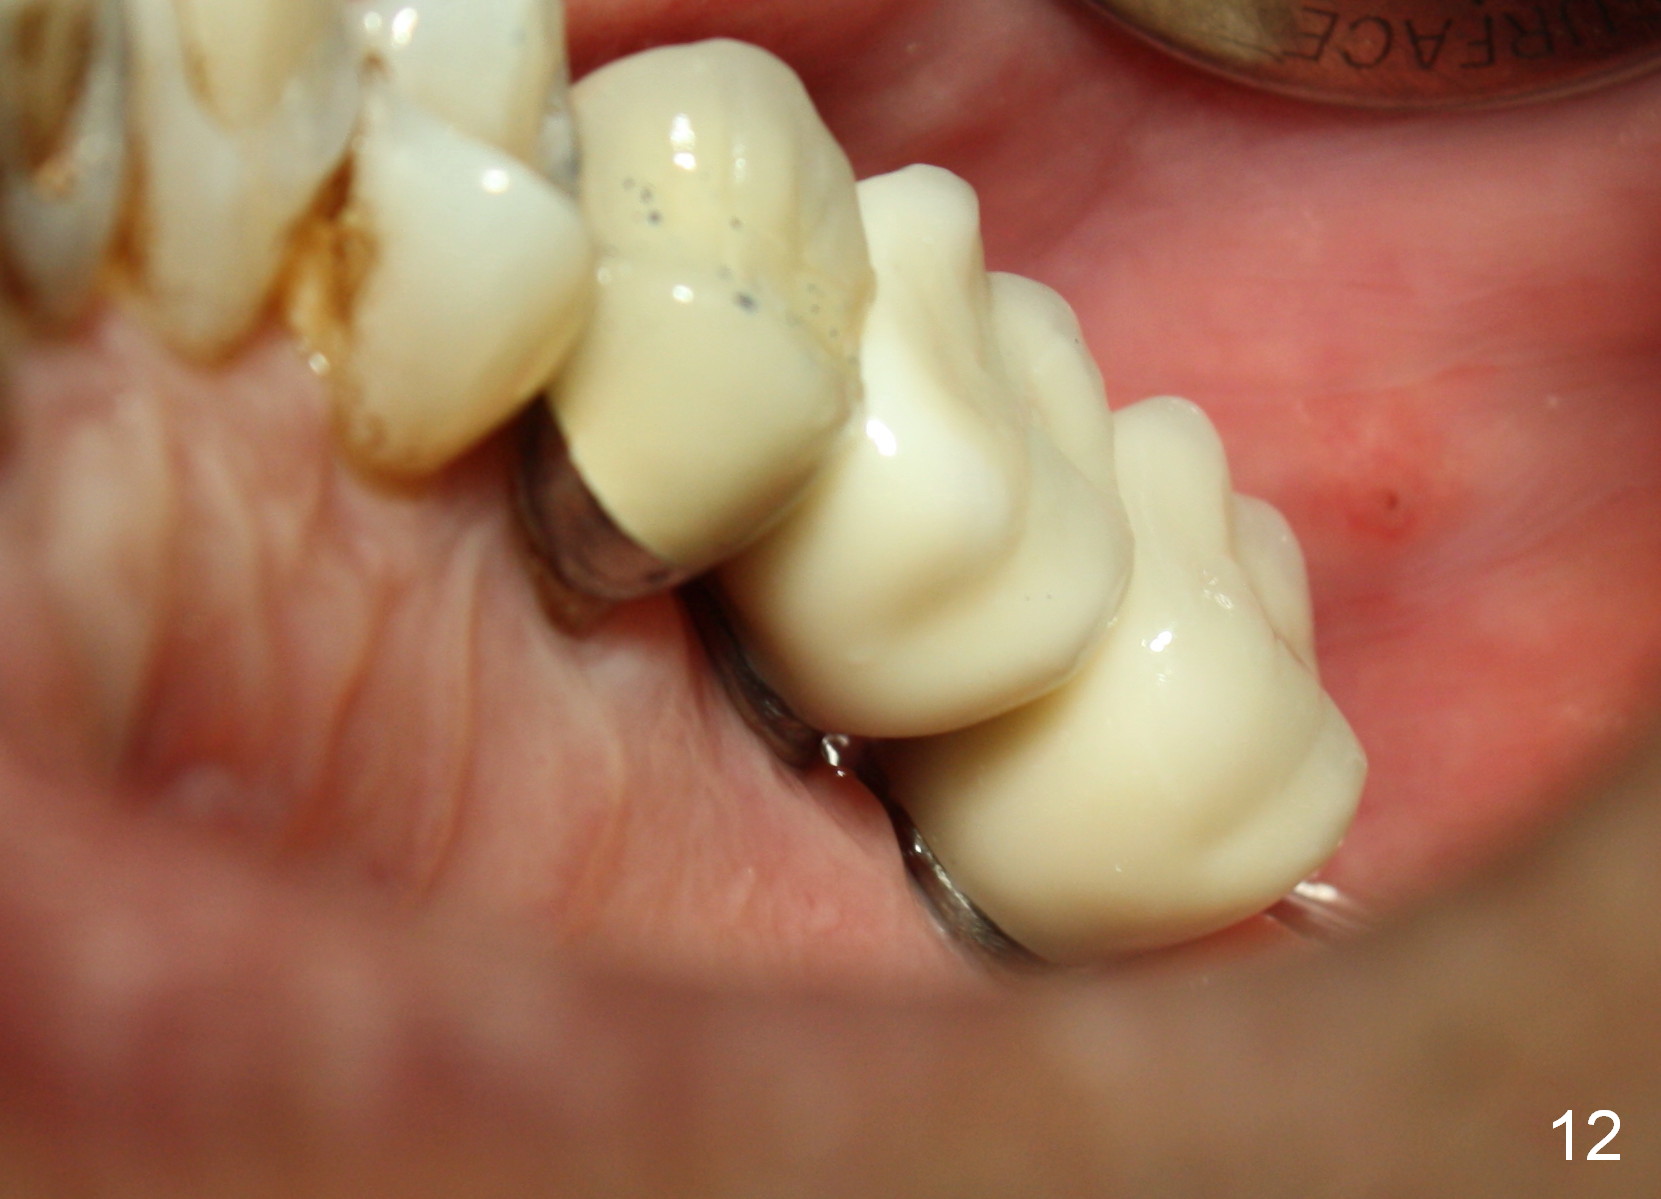

A 58-year-old man used to have a upper left 3-unit bridge. Two months after extraction and immediate implant at the site of the posterior abutment, an implant is planned to be placed at the site of the pontic, #14 (Fig.1). Osteotomy starts with a 1.6 mm pilot drill, followed by bone expanders, parallel to the crown of the tooth #13. The first intraop PA shows that 3.0 mm bone expander is close to the root of the neighboring tooth (Fig.2). No matter what is done to change the trajectory of the osteotomy using expanders according to the crown morphology of the neighboring tooth, the next 3 expander does not improve in parallelism (Fig.3). When a 6x17 mm tap is inserted (Fig.4 T), it is realized that axis of the tap is parallel to the axis of the crown of the neighboring tooth (black line), but not that of the root (red line). It is too late to change the trajectory drastically; a 6x17 mm implant is placed with insertion torque > 60 Ncm (Fig.5). It is best to change the trajectory as early as possible, e.g., after taking the first intraop PA and withdrawing the expander (Fig.6 black area) and as much as possible (red line; starting new osteotomy). It is quite similar to immediate implant. There is no bone loss 2 months postop (Fig.7), 18 months (Fig.8,9) or 34 months (Fig.10)post cementation, in spite of open contact between the crowns (Fig.10 black arrowhead). This is partially due to supragingival margin (Fig.11,12 (immediately pre-cementation)). No bone loss is noted 3 years 5 months post cementation (Fig.13).